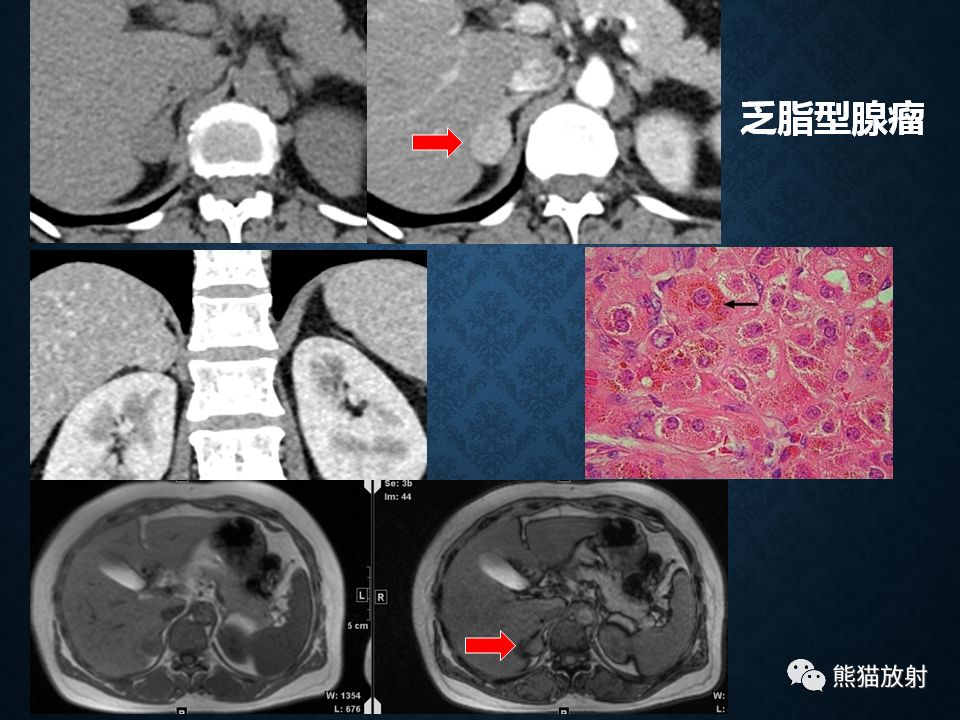

肾上腺常见肿瘤影像诊断

·也称:肾上腺性性征综合征

·临床上很少见

·皮质分泌过量雄性激素而导致女性假两性畸形或男性性早熟等病因:

>腺瘤:临床表现决定于肿瘤的发生年龄,与 Cushing腺瘤表现相同,但无对侧萎缩改变

>皮质癌:约占30%

>先天性肾上腺增生:双侧肾上腺腺体显著弥漫性增大,程度常明显超过 Cushing综合征的皮质增生